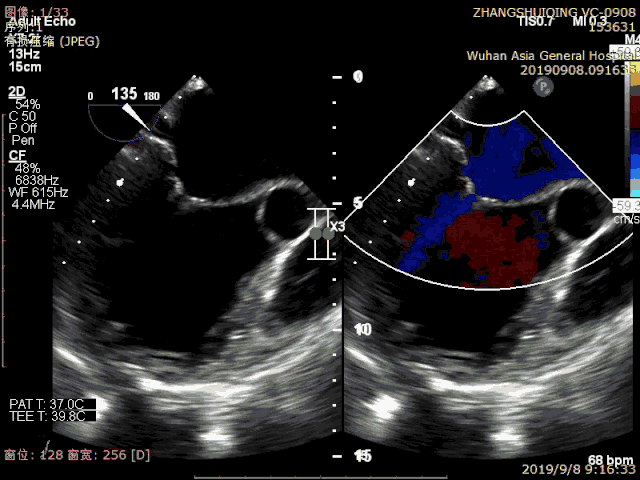

患者术前心超显示心脏扩大,严重脱垂